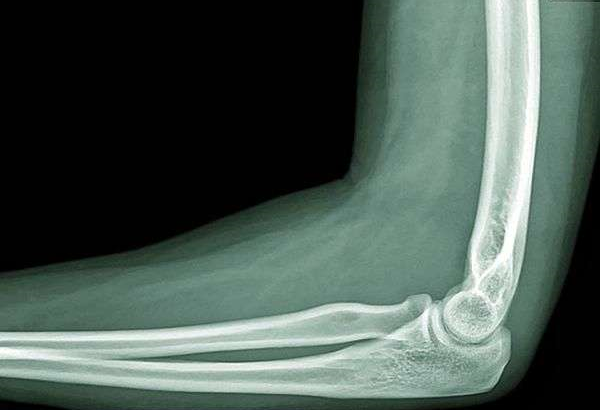

ПЕРЕЛОМ ЯКОЇ КІСТКИ І ЯКОЇ ЇЇ ЧАСТИНИ ВИ БАЧИТЕ НА РИСУНКУ?

варіанти відповідей

ДИСТАЛЬНОГО ДІАФІЗА

HUMERUS

ULNA

RADIUS

ПРОКСИМАЛЬНОГО ЕПІФІЗА

ДИСТАЛЬНОГО ЕПІФІЗА

ДІАФІЗА

МЕТАФІЗА